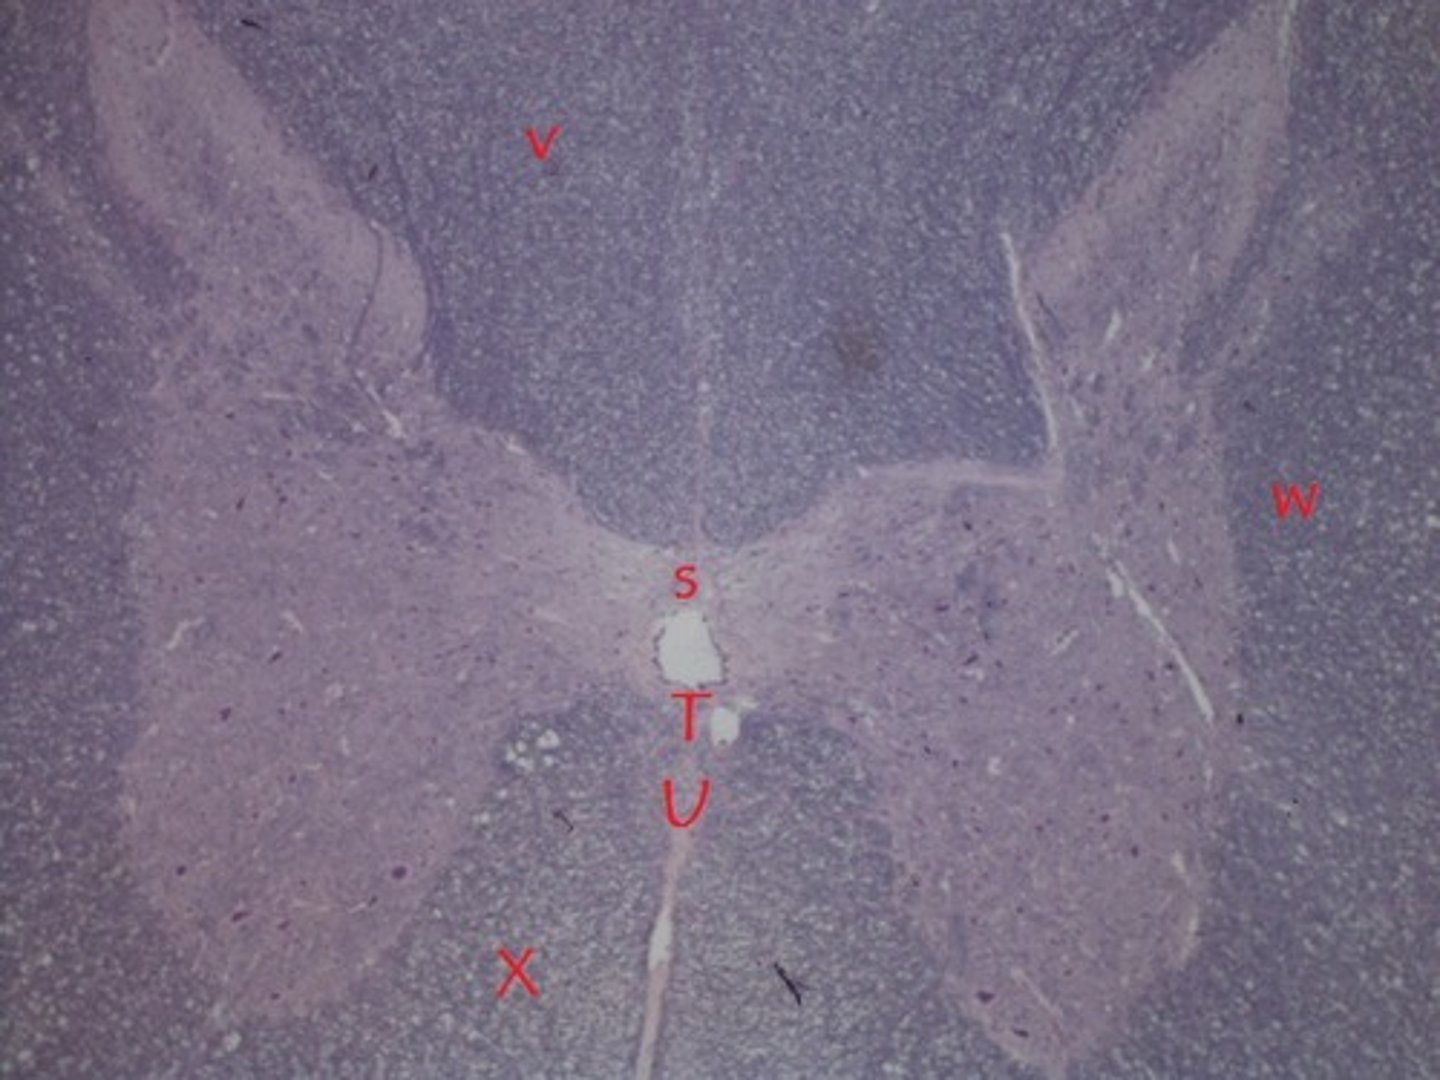

V

lateral white column

W

anterior white column

X